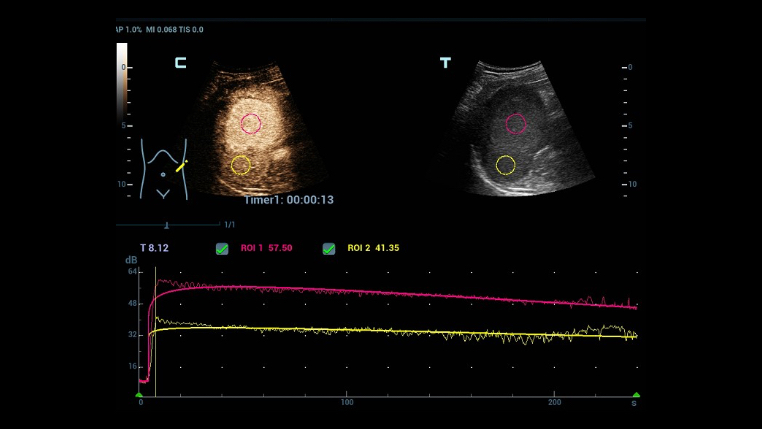

The channel data based ZST+ is an extraordinary innovation, representing an ultrasound evolution. Transforming ultrasound metrics from conventional beamforming to channel data based processing; ZST+ is able to deliver multiple imaging advances: Advanced Acoustic Acquisition, Dynamic Pixel Focusing, Sound Speed Compensation, Enhanced Channel Data Processing and Total Recall Imaging.

Channel data based ZST+ provides Enhanced Channel Data Processing for greatly improved imaging clarity. By multiple and retrospective channel data processing, it makes the best use of acoustic information for image improvement.

As ZST+ captures and stores the complete acoustic raw data set. Total Recall Imaging allows system to do retrospective processing on channel data and also permits users to modify numerous imaging parameters on stored images to maximize clinical output.